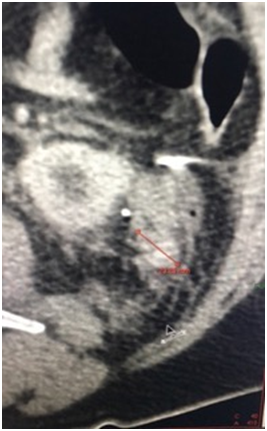

A 72 years old man was diagnosed with a small left renal mass incidentally during an ultrasonography for to an aortic abdominal aneurysm. A computer tomography (CT) scan confirm an exophytic 3cm left renal mass; therefore, an unclamped-laparoscopic partial nephrectomy was performed without difficulty. The tumor was placed inside of a plastic self-performed thermofused retrieval bag (Figure 1) and extracted trough a 12mm laparoscopic port. Finally, a drain was also placed close to the renorrhaphy. The patient was taken to the hospital room and in that moment, we realized that the bag was broken and the tumor was not inside. With the patient and family consent, a CT scan was performed showing a small mass next to the renorrhaphy (Figure 2); therefore, we decided to underwent an exploratory laparoscopy using the same port and patient position. Once laparoscopic camera was introduced, the tumor was found over the sigmoid colon slightly adhered (Figure 3) and extracted inside of a surgical glove. The hospital stay was 3 days with no perioperatory complications and the final histopathological finding was a 2cm cromophobo renal cell carcinoma with negative surgical margins.

Figure 2 Computer Tomography show the small renal mass close to the renorraphy.